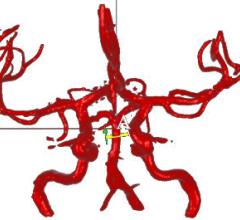

Pie Medical Imaging BV announced that it received 510(k) clearance from the U.S. Food and Drug Administration for its CAAS A-Valve product including the quantitative Regurgitation Analysis (qRA) workflow. The qRA workflow is the first 510(k) cleared image analysis technology to determine aortic regurgitation based on X-ray angiography.